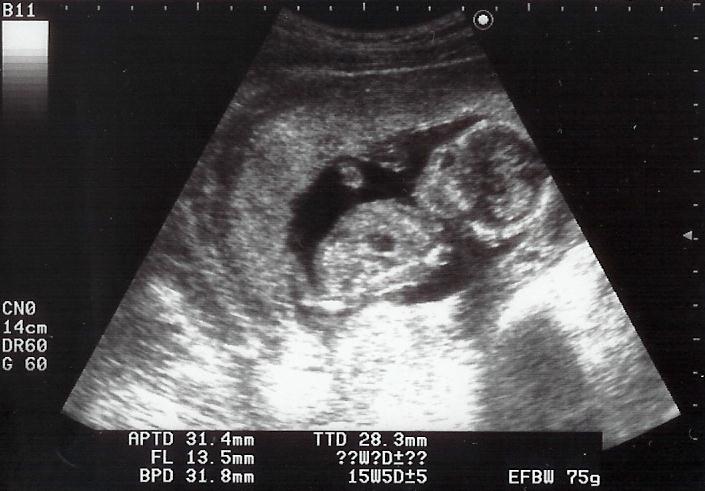

2004年10月29日(金)

15週0日

パパはママと一緒に病院へ行きました。初めて動いているshigeruとご対面。パパの感想は・・・可愛いですね。元気元気!